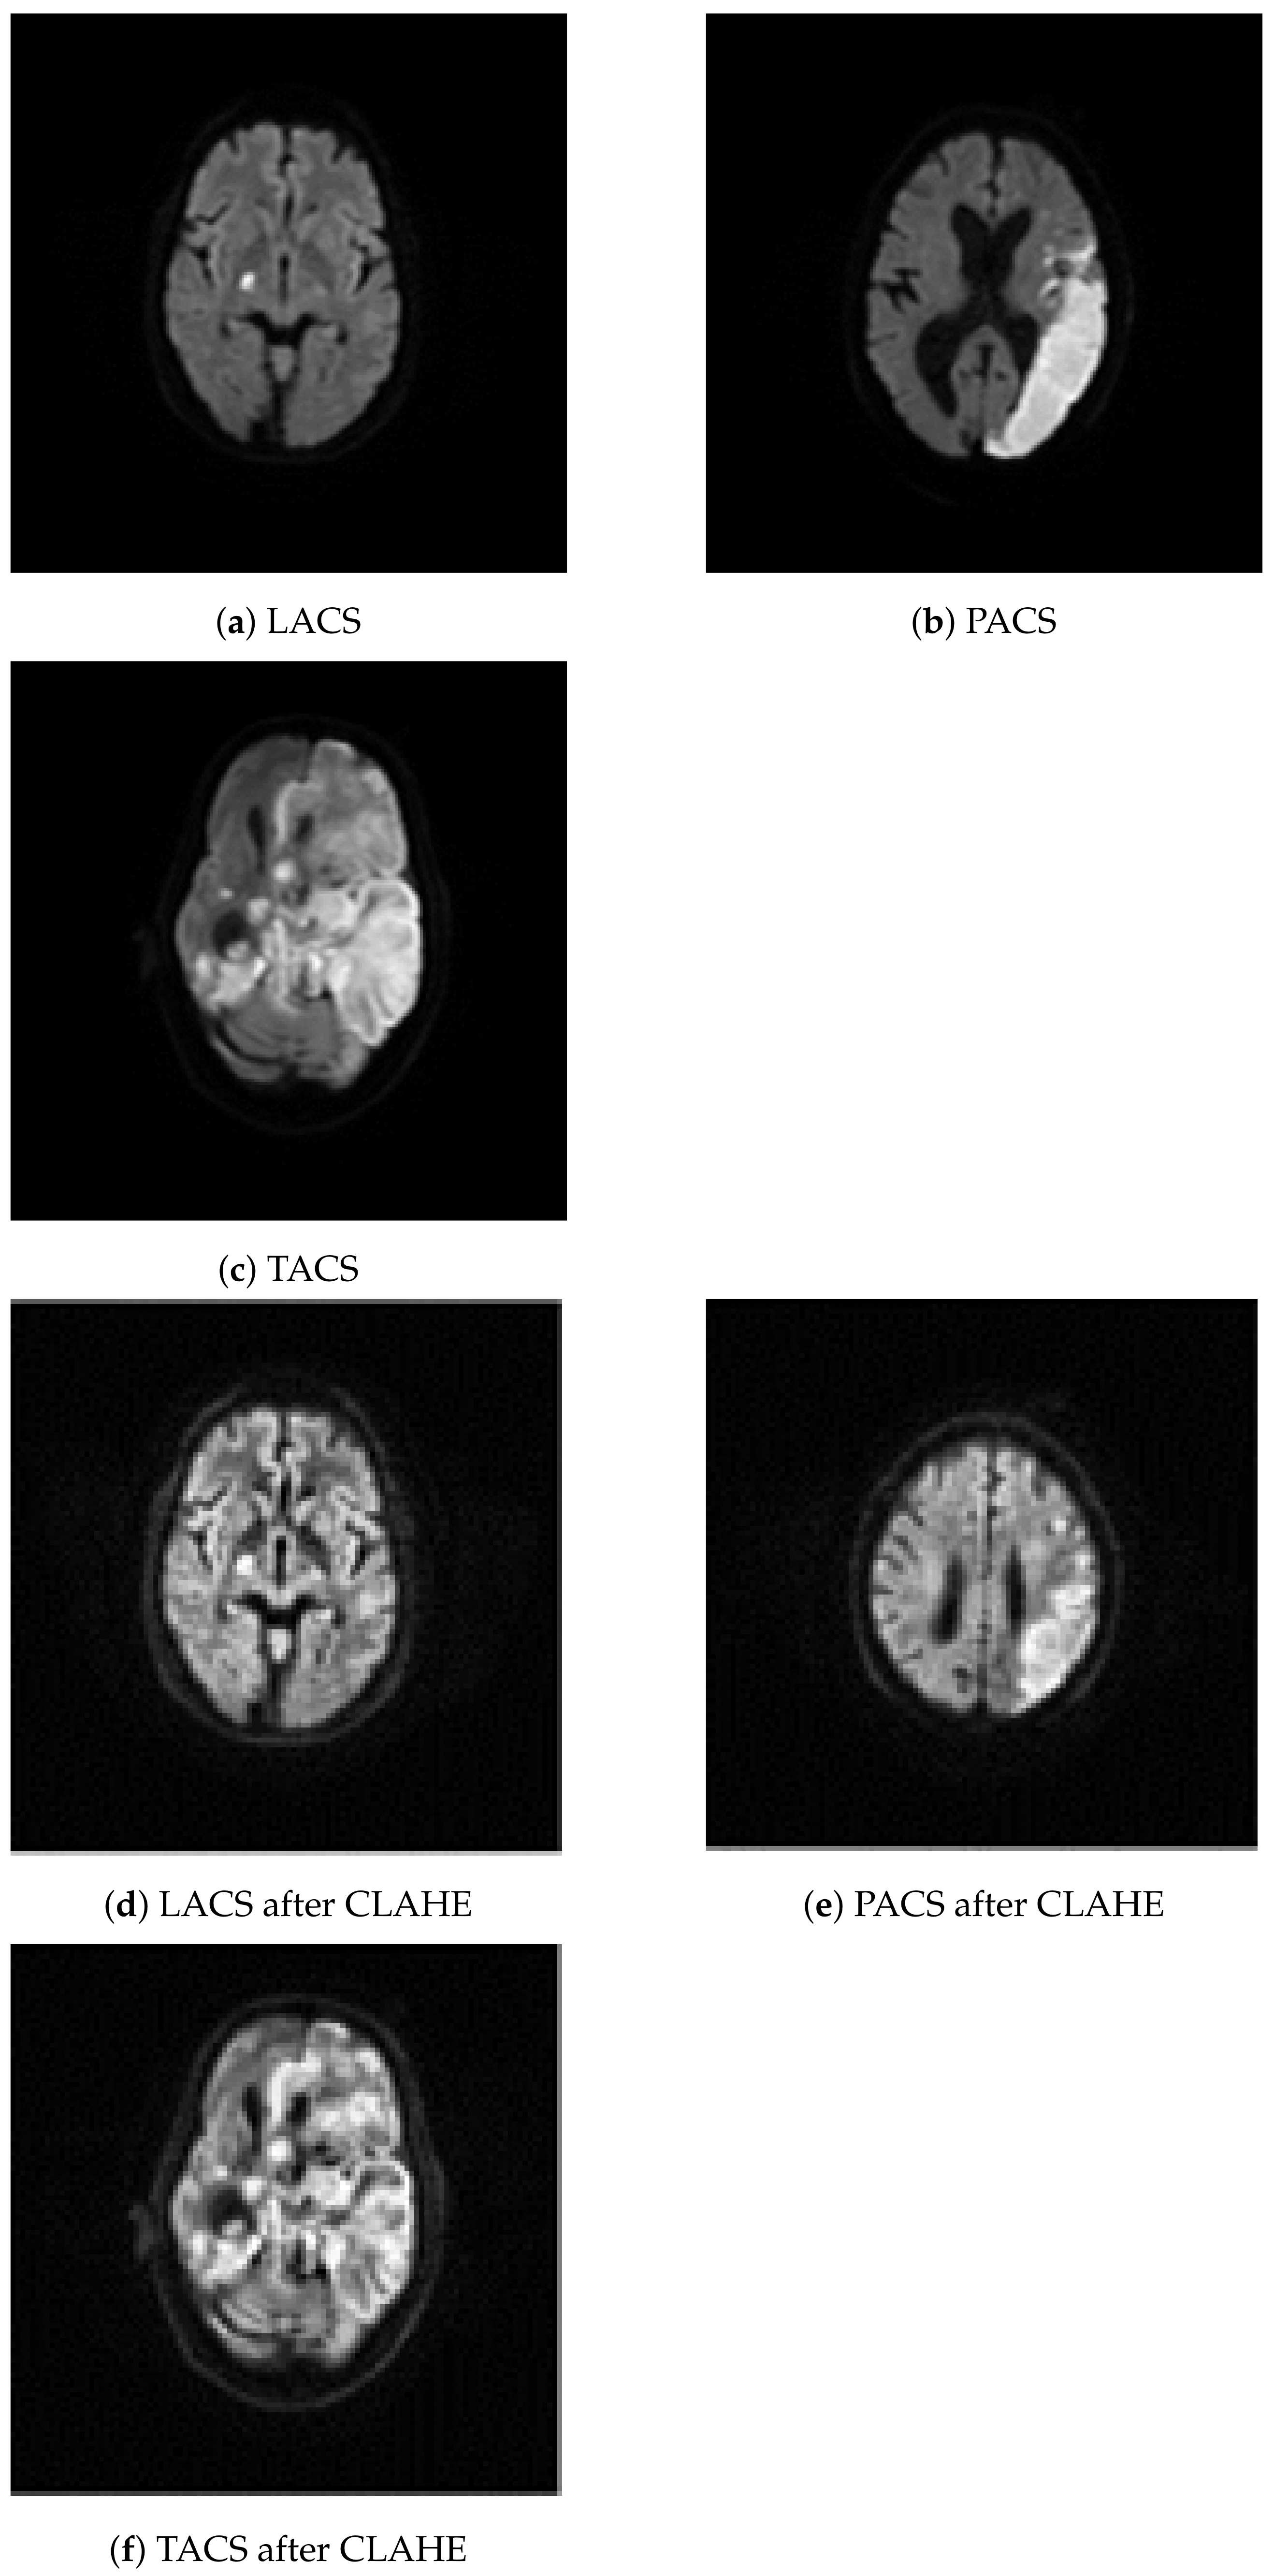

We have considered 267 slices (PACS 222, LACS 18, and TACS 27) of brain MRI datasets collected from ischemic stroke patients at the Institute of Medical Science and SUM Hospital, Bhubaneswar, Odisha, India. The data was anonymised such that even basic demographics, like age and gender of the patients, are not available. Experts at the hospital selected a single diffusion weighted slice from all the MRI images that were taken during one imaging session from a stroke patient. The selected slices show the stroke lesion and they were used by human experts to support the diagnosis of PACS, LACS, and TACS, on the basis of the clinical features of the patients. The MRI images of the affected brain were acquired with the Signa HDxT 1.5 T Optima Edition machine (GE Healthcare, Waukesha, WI, USA). The first row of images in Figure 2 shows three example MRI images depicting LACS, PACS, and TACS.

Figure 2.

Class specific examples from the image dataset. The original images are shown in the first row: (a–c). The images were created by processing the original images with contrast adaptive histogram equalization: (d–f).

In a first processing step, we resized all 267 MRI images to 200 × 200 pixels. Subsequently, CLAHE was used to increase the difference in luminance which improves visual feature detection. That was necessary because the brain tissue, shown in the MRI images, lacks contrast, which makes it more difficult to distinguish texture morphology. CLAHE is based on histogram equalization, which can help to increase the prominence of textural changes caused by lesions, via contrast enhancement [43]. Adaptive histogram equalization starts with partitioning an image into nonoverlapping 8 × 8 pixel segments known as tiles. Each tile is enhanced so that the resulting histogram matches a uniform distribution. That process is governed by the contrast enhancement limit (0.01), which prevents over-saturation in uniform image regions. Manipulating the tiles independently might introduce artificial boundaries between them. Therefore, in a final processing step, we used bilinear interpolation to smooth the boundaries. The second row of images in Figure 2 shows the example MRI images after CLAHE.